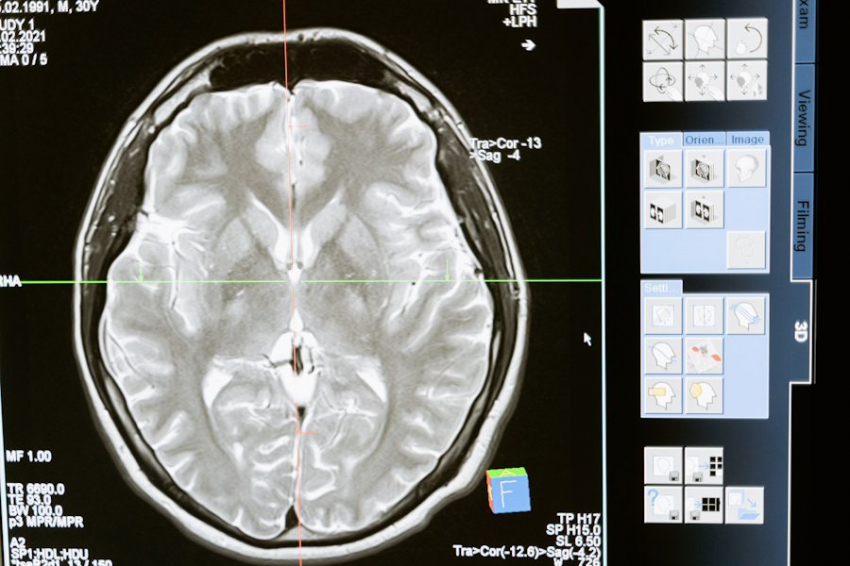

Фото из открытых источников

Ученые из Объединенного института ядерных исследований (ОИЯИ) разработали уникальную программу для прогнозирования радиационного воздействия на нервные клетки. Это достижение открывает новые возможности в области радиобиологических исследований и оценки влияния различных видов ионизирующего излучения на центральную нервную систему.